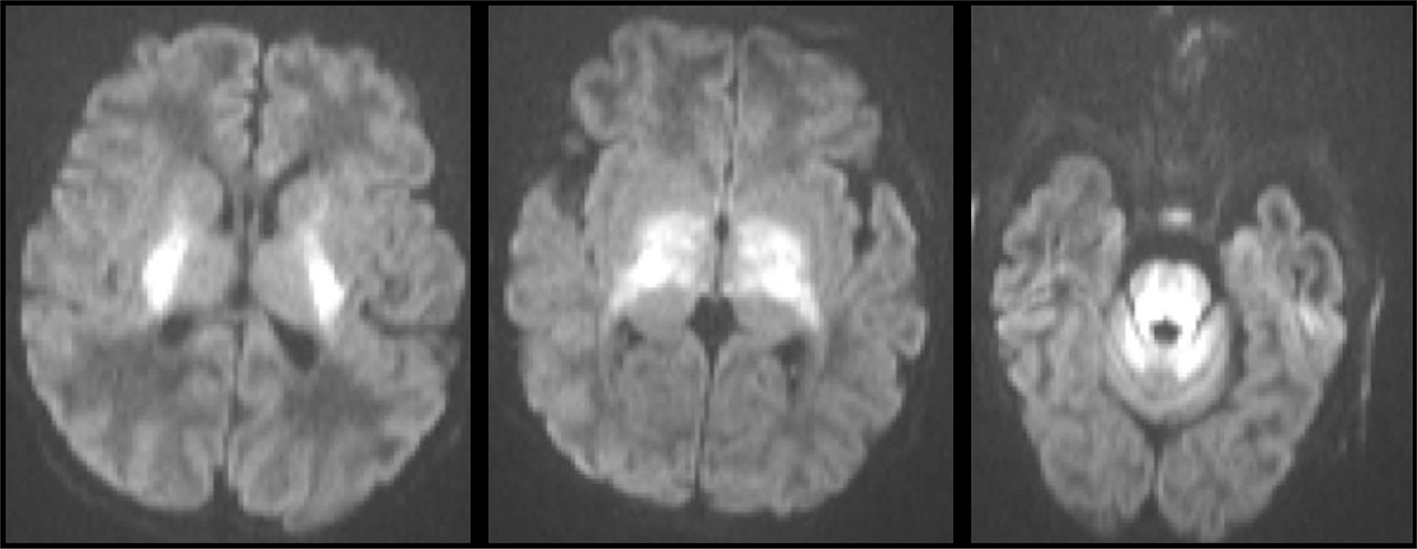

Fig 12

Figure 12. A three-weeks-old girl with seizures and hypoglycemia. Axial CT (A) and axial DWI (B), and ADC (C) MR images show low density and loss of gray-white matter differentiation in the posterior half of the cerebral hemispheres on CT and reduced diffusion on MRI. The extent of the signal abnormality is much greater than usually seen with watershed infarction in the border zone between the MCA and PCA. Case courtesy of Dr. Tamara Feygin, Department of Radiology, Children’s Hospital of Philadelphia.